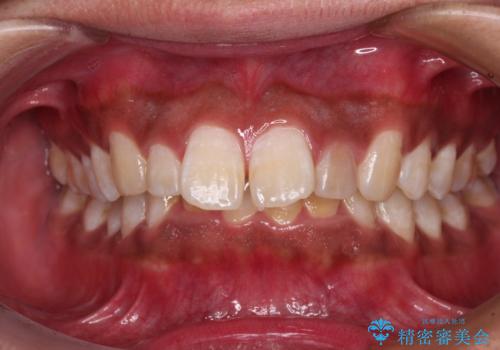

- 深く咬みこみ、前に飛び出した上顎前歯を気にして来院された患者様です。

口元の突出感はあまりありませんでしたが、上顎歯列が全体的に前方にあり、更には下顎歯列が深く咬みこんでいるために、上顎前歯が前方に突出している状態でした。